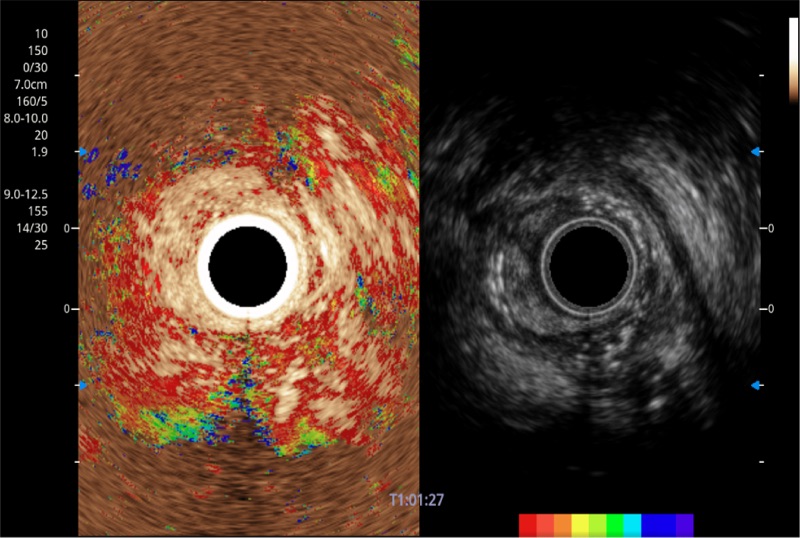

可人为将灰阶图像转变成彩色的显示方式,增强人眼对于不同回声强度的敏感度,主观上增加了图像分辨率

食管内间质瘤清晰显像